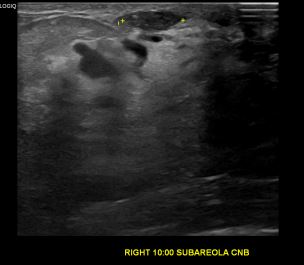

상기환자는 외부검진이상소견  조직검사위해 내원하신 40대 초반

여성분으로 의심스러운 우측유방혹 조직검사 시행해 상피내암으로 진단되었습니다.